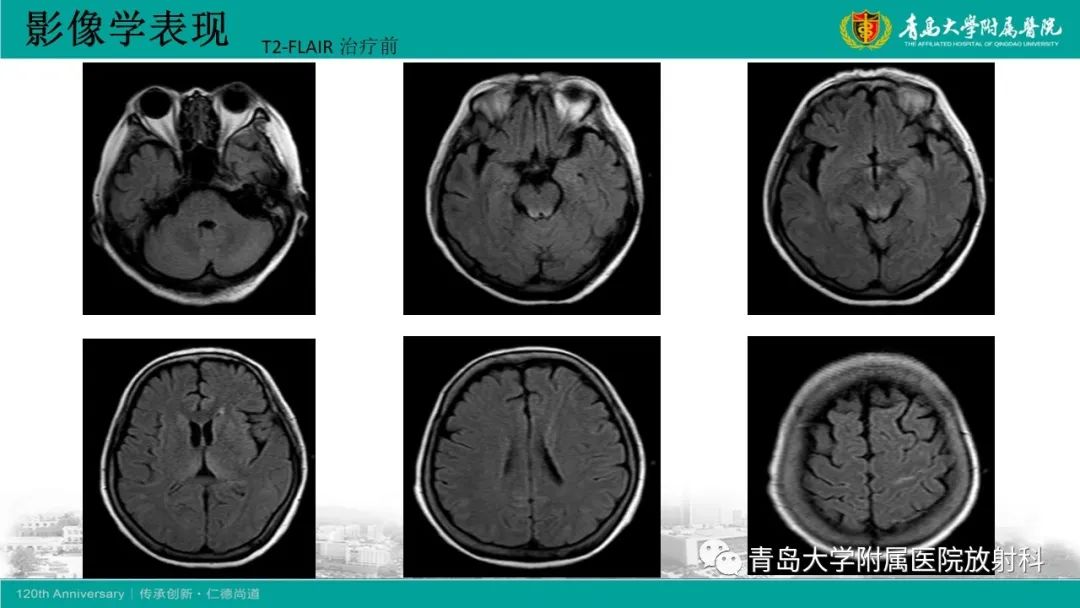

Wernicke脑病1例MR影像

【病例】Wernicke脑病1例MR影像-1